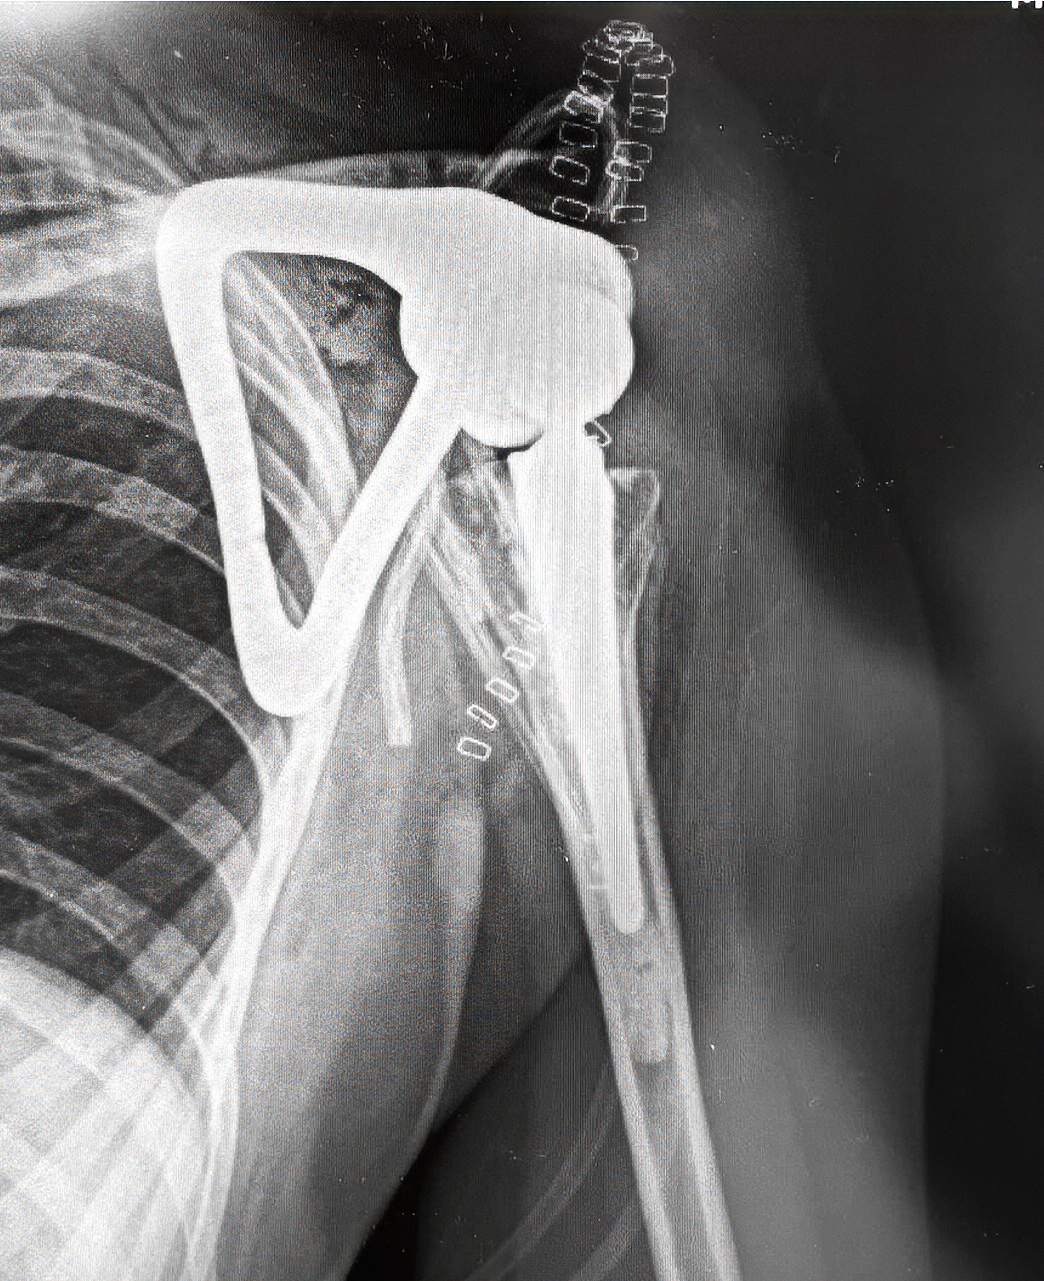

Postoperative radiograph confirming stable reconstruction and anatomical alignment.

Following complete tumor resection, the custom scapula prosthesis was implanted according to the preoperative plan. Postoperative X-rays confirm stable positioning and correct alignment of the reconstruction. The anatomical relationship between the custom scapular body and the humeral component demonstrates precise execution of the surgical and engineering concept.

The reconstruction achieved structural stability and provided a defined articulation, creating the basis for functional recovery. Most importantly, the implant design allowed systematic soft-tissue reattachment, which is indispensable for long-term shoulder function in total scapula replacement cases.